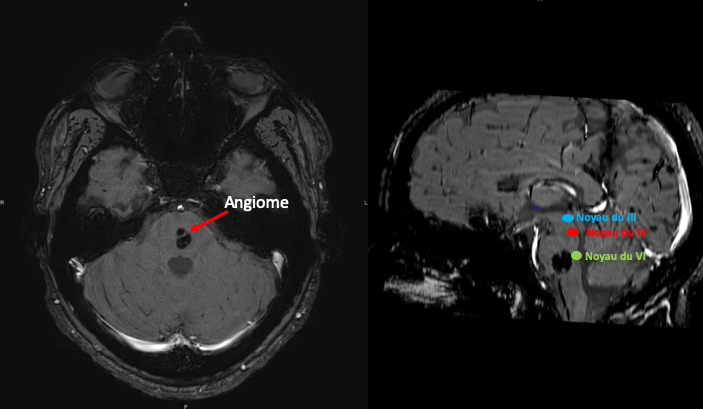

Vous demandez une IRM cérébrale injectée dont voici 2 clichés. La lésion du tronc cérébral est identifiée comme étant un angiome sans signe de saignement récent.

Source : M. Philibert.

L’IRM cérébrale retrouve une lésion du tronc cérébral qui est un angiome. Cependant, il est situé au niveau du pont alors que le noyau du III est situé à la partie haute du mésencéphale, il ne peut donc pas être en cause dans la paralysie. Le reste de l’IRM est normale. Il n’y a donc pas d’anomalie morphologique permettant d’expliquer le tableau clinique.

L’IRM cérébrale ne retrouve pas de lésion permettant d’expliquer le tableau clinique. L’angiome protubérantiel est à distance du noyau du III et n’est pas responsable du tableau clinique.